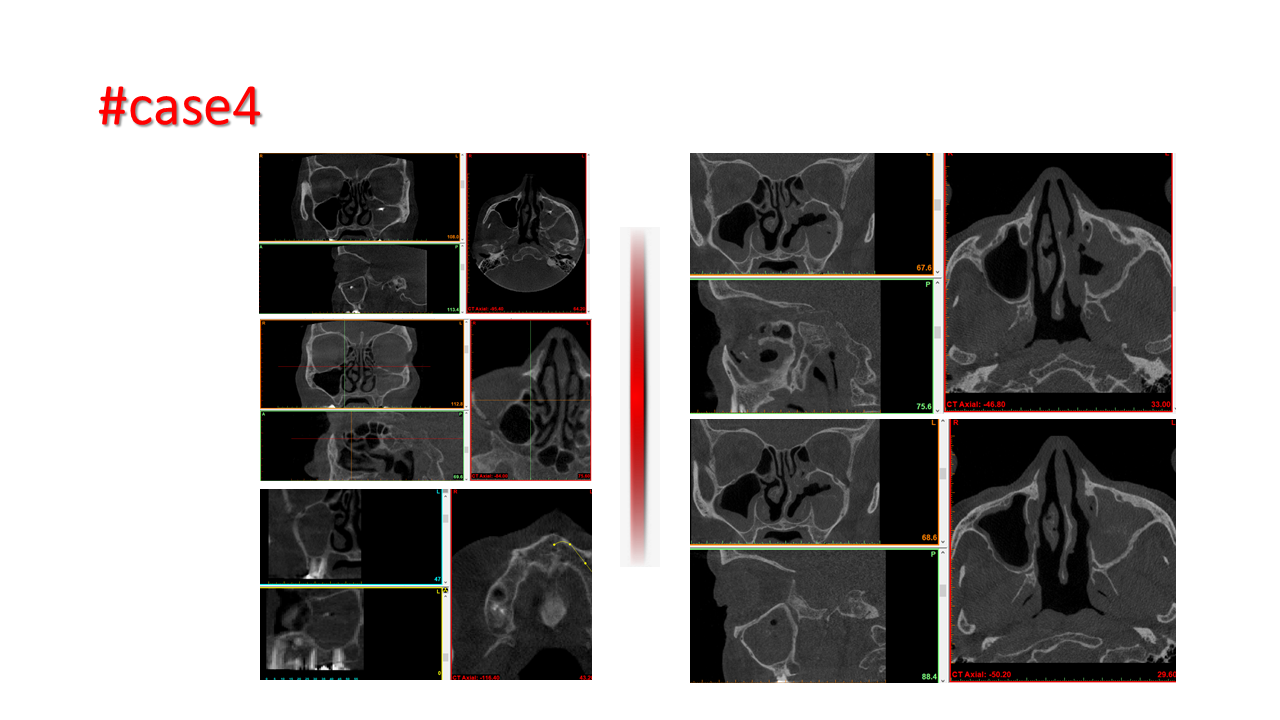

FESS Case Review and Radiologic Analysis (30.09.2016)

Case-based presentation focused on pre- and postoperative imaging in functional endoscopic sinus surgery (FESS). Includes anatomical landmarks, surgical variations, sinus pathology, and technique evaluation. Delivered by Dr. Levon Galstyan at AAOMFS.